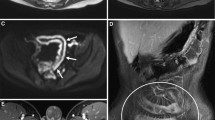

As mentioned before, MRI can be used for the evaluation of extramural disease. Due to the high contrast resolution abscesses are very conspicuous on T1-weighed fat suppressed images after the administration of intravenous Gadolinium. MRI is also very sensitive for the detection of fistulas [47, 52, 58] (Fig. 9).

Extramural manifestations of disease that can be identified on MRI are fistulas, abscesses, fibrofatty proliferation, and enlarged lymph nodes.

Imaging criteria

A bowel wall thickness exceeding 3 mm should be considered as an indicative of disease. Besides bowel wall thickening the most important criterion indicative of active IBD is pathological bowel wall enhancement after the administration of intravenous gadolinium. Bowel wall enhancement can always be seen as the bowel is a highly vascularized structure. However, in active IBD increased enhancement can be observed, due to the increased vascularization and the increased capillary leakage of the affected tissue (Fig. 8). In CD it has been hypothesized that the degree of enhancement correlates with the degree of disease severity, but this statement has not been extensively corroborated [50–53].

A 12-year-old male patient with known CD who underwent MR-enterography for the evaluation of the small bowel (same patient depicted in Fig. 6b). Axial T1-weighted image shows pathological enhancement of thickened small-bowel loops after administration of intravenous contrast medium (arrowheads). Approximately, 1 m of small bowel (terminal jejunum, proximal ileum) was shown to be affected.

Bowel wall stratification can be observed on T2-weighted images as a bright line within the two dark stripes of the mucosal and muscularis propria layers, likely related to the presence of fat or edema in the submucosal layer. On fat-suppressed T2-weighted images it is possible to determine the nature of the bright signal as a persistent bright signal suggests the presence of edema, whereas complete suppression of the submucosal signal suggests fat infiltration and quiescent disease [54].